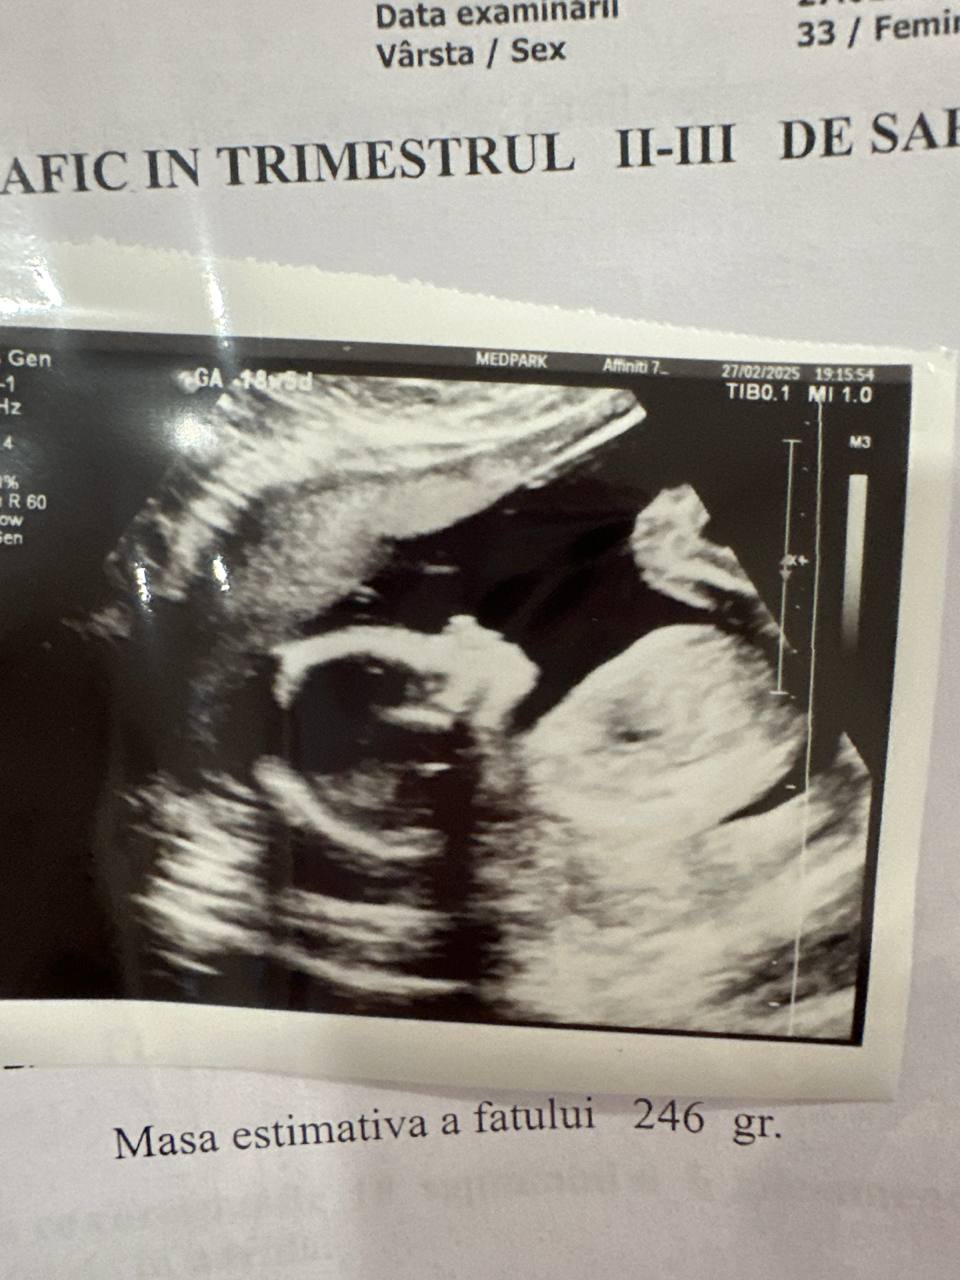

Передо мной большой экран и каждый раз глаза на мокром месте. Не могу поверить в то, что вижу, моя малышка живет там своей жизнью, придумывает чем себя занять: то зевает, то руки в рот кладет, ножкой дрыгает. Я никогда не думала, что смогу так любить еще не родившегося ребенка.

Посмотрели кажется все: шейка 38 мм и закрылась (господи, она была открыта по всей длине на 3-5 мм весь первый триместр), плацента в порядке, воды чистые и достаточное количество, все кровотоки в норме. Мозг, сердечко, желудок, позвоночник, почки, мочевой, все косточки, пальчики, все показали на экране. Все 4 камеры сердца вывели на огромный экран и смотрели, как оно гоняет кровь🙈 Фантастика просто.

Узистка была очень довольна всем, сказала, что все уже сформировано, отклонений нет, все очень хорошо. Дали фото на память и отпустили до 28 недели) Но я конечно приду в промежутке еще посмотреть, что все ок))